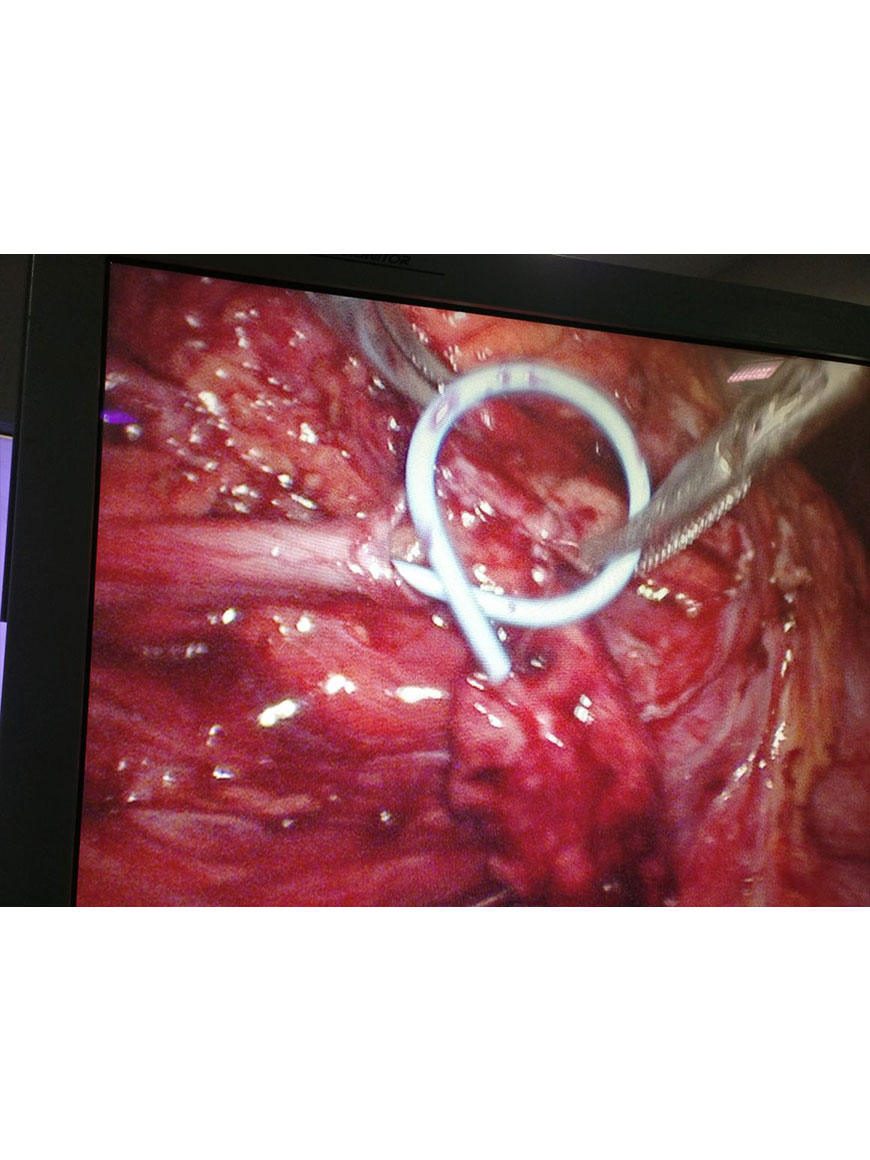

Radical Nephrectomy